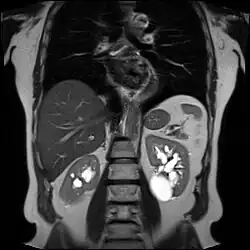

| Renal cyst of the left kidney (hyperintense area) as shown on MRI. | |